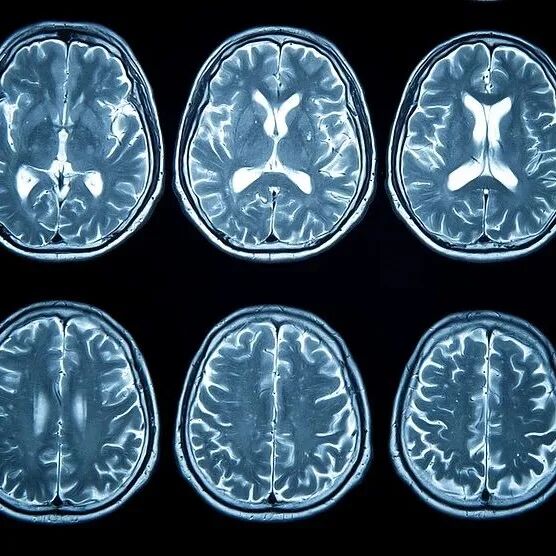

脑梗又称“缺血性脑卒中”,是由于脑血管阻塞,导致脑部血液循环障碍,缺血缺氧引起的局部脑组织缺血性坏死。发病时,患者可表现为语言障碍、肢体麻木、视物异常及头晕头痛等。